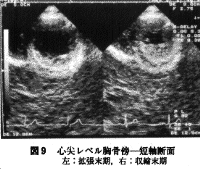

次いで徐々に探触子を心尖方向を見るように傾けていくと(左室腔が楕円とならず正円となるように必要に応じて肋間の移動も行う)、僧帽弁レベル、腱索レベル、乳頭筋レベル、心尖レベル(図6,7,8,9)と順次各レベルでの短軸断面が観察されるので2)の観察ポイントに注意しながら断面を描出していく(左室短軸断面の静止画を記録する場合は壁運動評価もある程度可能な拡張末期と収縮末期の2時相が適している)。

j)心尖部では収縮期の内腔の消失はないか